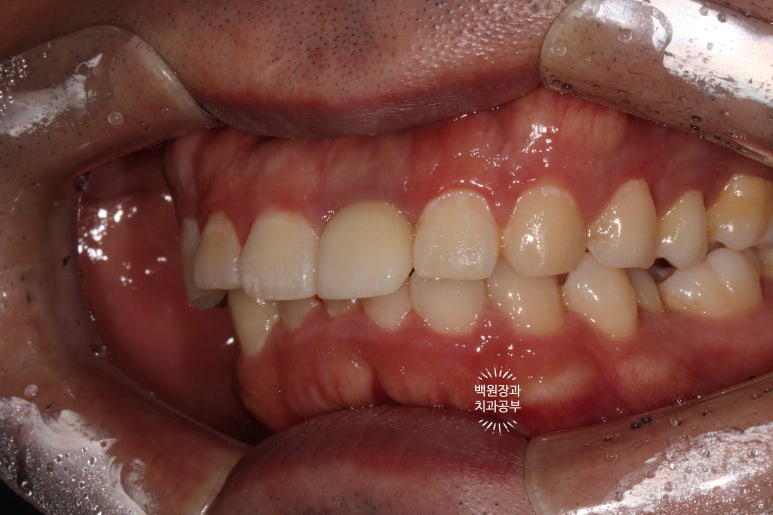

옆에서 보면 왠지 치아 주변이 조금 검은듯한 느낌이 들기는 하나,

바로 옆에 위치한 또다른 가운제 앞니와 비교했을 때 큰 차이 없이 적절한 외형의 임플란트 보철물을 보실 수 있어요.